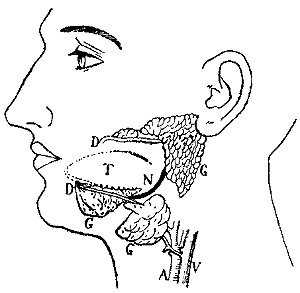

10 The Salivary Glands

The Salivary Glands. Now, where does this saliva in the mouth come from? It is poured out from the pouches of the cheeks, and from under the tongue, by some little living sponges, or juice factories, known as salivary glands.[2]

In this diagram are shown the three glands (G) of the left side. The duct (D) from the parotid gland empties through the lining of the cheek; those from the lower glands empty at the front of the mouth under the tongue (T). N, nerve; A, artery; V, vein.

All the juices poured out by these glands, indeed nearly all the fluids or juices in our bodies, are either acid or alkaline. By acid we mean sour, or sharp, like vinegar, lemon juice, vitriol (sulphuric acid), and carbonic acid (which forms the bubbles in and gives the sharp taste to plain soda-water). By alkaline we mean "soap-like" or flat, like soda, lye, lime, and soaps of all sorts. If you pour an acid and an alkali together—like vinegar and soda—they will "fizz" or effervesce, and at the same time neutralize or "kill" each other.

The Use of the Saliva. As the chief purpose of digestion is to prepare the food so that it will dissolve in water, and then be taken up by the cells lining the food-tube, the saliva, like the rest of the body juices, consists chiefly of water. Nothing is more disagreeable than to try to chew some dry food—like a large, crisp soda cracker, for instance—which takes more moisture than the salivary glands are able to pour out on such short notice. You soon begin to feel as if you would choke unless you could get a drink of water. But it is not altogether advisable to take this short cut to relief, because the salivary juice contains what the drink of water does not—a ferment, or digestive substance (ptyalin), which possesses the power of turning the starch in our food into sugar. As starch is only very slowly soluble, or "meltable," in water, while sugar is very readily so, the saliva is of great assistance in the process of melting, known as digestion. The changing of the starch to sugar is the reason why bread or cracker, after it has been well chewed, begins to taste sweetish.

This change in the mouth, however, is not of such great {12}importance as we at one time thought, because even with careful mastication, a certain amount of starch will be swallowed unchanged. Nature has provided for this by causing another gland farther down the canal, just beyond the stomach, called the pancreas, to pour into the food tube a juice which is far stronger in sugar-making power than the saliva, and this will readily deal with any starch which may have escaped this change in the mouth. Moreover, this "sugaring" of starch goes on in the stomach for twenty to forty minutes after the food has been swallowed.